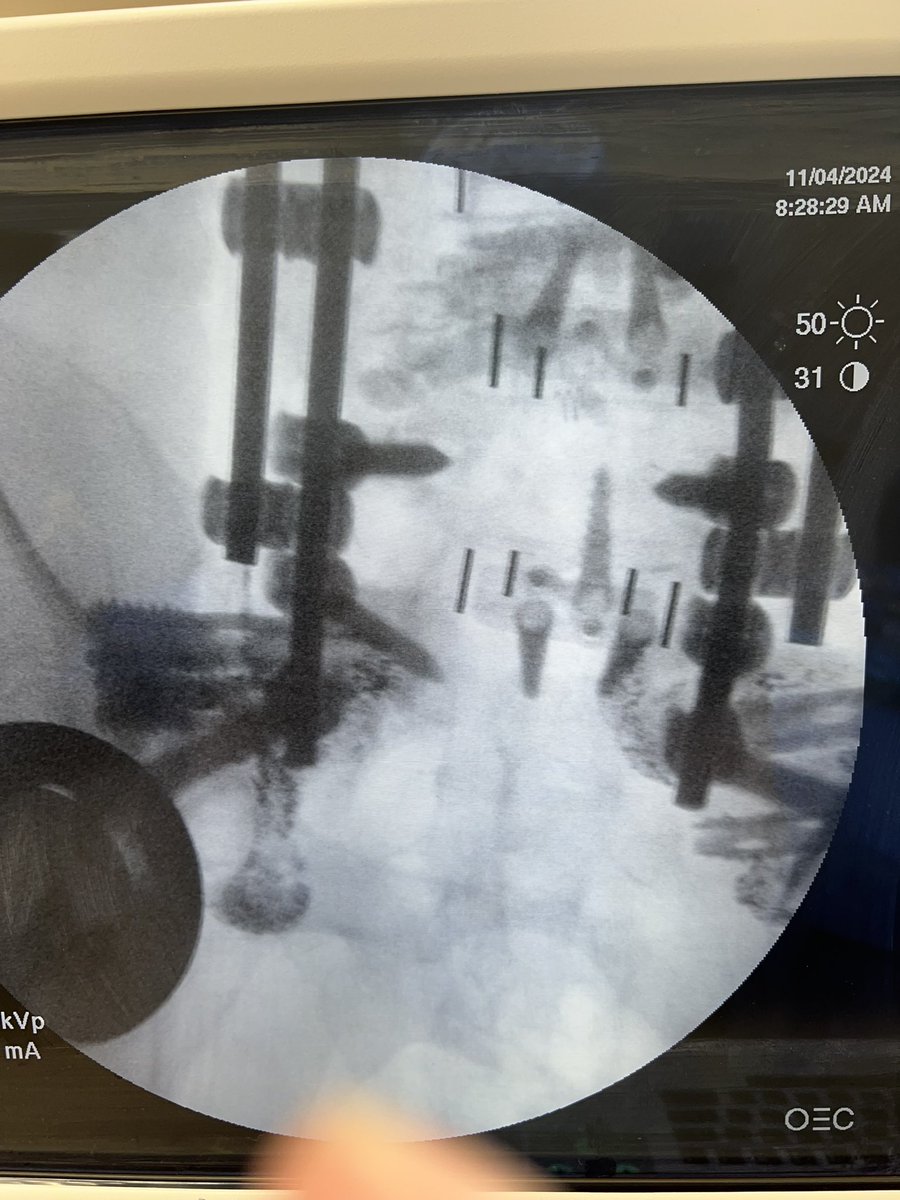

@TheStrykerIVS makes a great product, #SpineJack, that shows up in a lot of cool posts on this and other platforms.

This example was just posted by @neuroradiology - a great example of the genre.